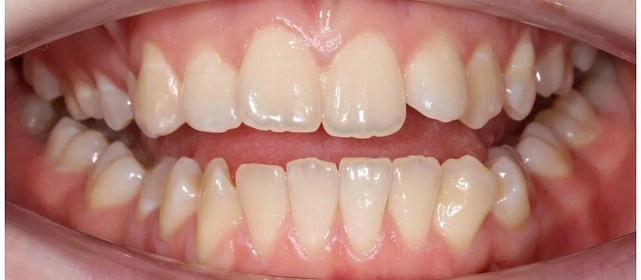

Диагностика

Верхняя челюсть выступала вперёд относительно нижней с обеих сторон (II класс по Энглю). Обе челюсти сужены, зубы стояли скученно. Нарушена кривая смыкания — жевательные зубы были на разной высоте. На двух передних зубах верхней челюсти ранее установлены металлокерамические коронки.

Проблема: Пациентку беспокоили неровные зубы и неправильный прикус. При осмотре нашли сразу несколько проблем: обе челюсти сужены, зубы стоят скученно, верхняя челюсть выступает вперёд (II класс по Энглю), кривая смыкания деформирована — жевательные зубы на разной высоте. На двух передних зубах верхней челюсти стояли старые металлокерамические коронки, которые нужно было учитывать при планировании.